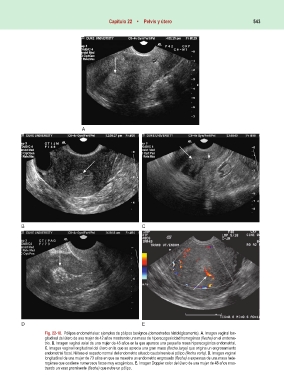

Fig. 22-18. Pólipos endometriales: ejemplos de pólipos benignos (demostrados histológicamente). A. Imagen vaginal lon-

gitudinal del útero de una mujer de 42 años mostrando una masa de hiperecogenicidad homogénea (flecha) en el endome-

trio. B. Imagen vaginal axial de una mujer de 48 años en la que aparece una pequeña masa hiperecogénica endometrial.

C. Imagen vaginal longitudinal del útero en la que se aprecia una gran masa (flecha larga) que origina un engrosamiento

endometrial focal. Nótese el aspecto normal del endometrio situado caudalmente al pólipo (flecha corta). D. Imagen vaginal

longitudinal de una mujer de 73 años en que se muestra un endometrio engrosado (flecha) a expensas de una masa hete-

rogénea que contiene numerosos focos muy ecogénicos. E. Imagen Doppler color del útero de una mujer de 48 años mos-

trando un vaso prominente (flecha) que nutre un pólipo.